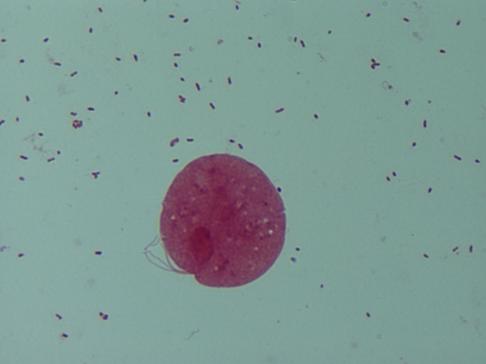

Fig. 21.5.5.1: Lactobacillus spp. (coloratie Gram, x1000, imagine din colectia proprie a laboratorului)

Aspect normal al unui prelevat vaginal: prezenta a numeroase celule epiteliale pavimentoase, polimorfonucleare putine, bacili Doderlein